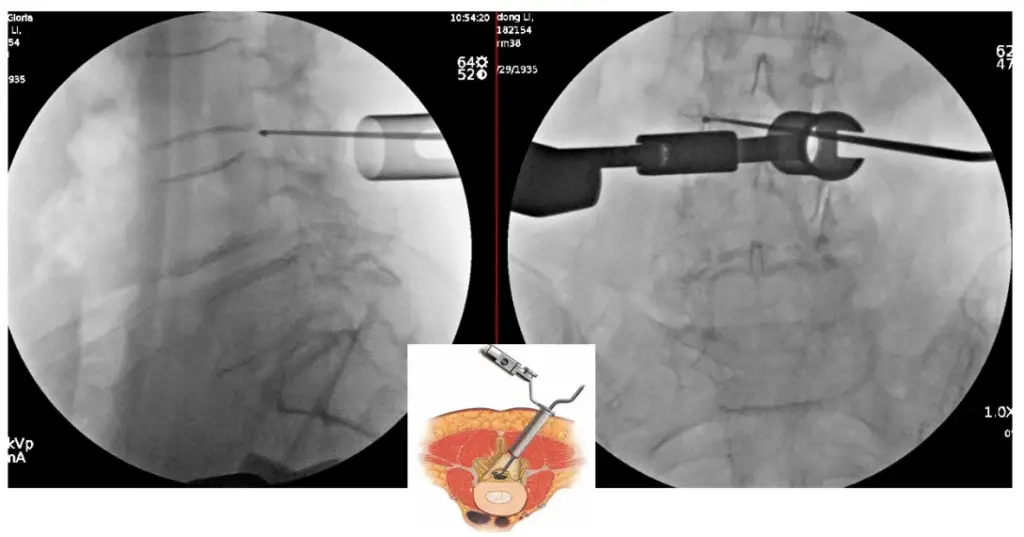

ULBD